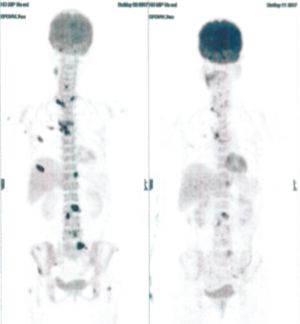

CASE NO: 7 (BREAST CANCER)

A middle-aged woman treated for breast cancer now presents with bone and liver metastases. After a few treatment, most of the cancer went into remission, and the remaining ones are less active.

CASE NO: 8 (BREAST CANCER)

A middle-aged women treated for breast cancer now present with bone and right lung metastases. After just 2 treatment, almost all the cancer went into remission, but treatment is continuing to prevent recurrence.

CASE NO: 9 (NHL + LUNG CANCER)

A middle-aged man successfully treated for non-Hodgkin’s lymphoma, came back with massive right lung and pleural cancer. After just 2 treatment, all the cancer went into remission. Treatment is continuing to prevent recurrence.

CASE NO: 10 (LUNG CANCER)

An old man with right lung cancer refused all cancer treatment, but was convinced to try our new cancer treatment because there is no severe side effect. After 3 treatment, the cancer shrunk to less than half the original size. He did not come back to continue the treatment.